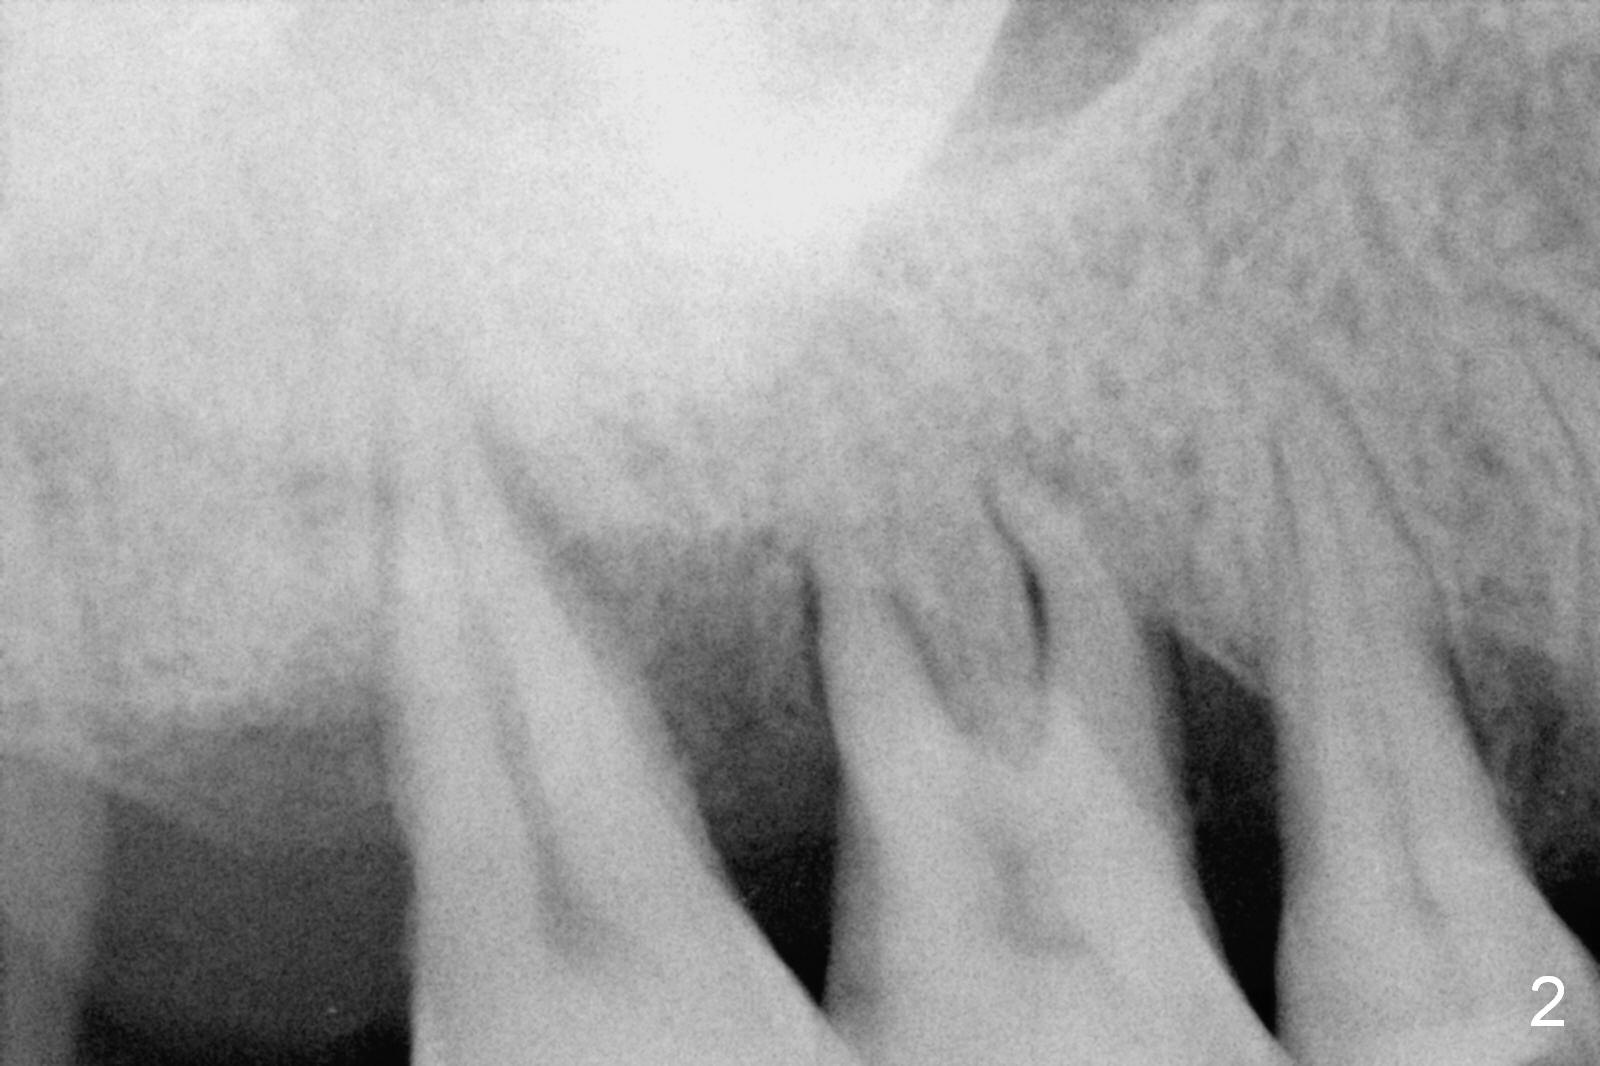

A 52-year-old lady is pleased with the implant at #15 and requests implants at #2 and 3 next (Fig.1,2). Due to severe bone resorption, bone level should be uneven circumferentially. The implants will be placed as apical as possible, i.e., buried in the native bone. If implant threads are exposed in small region, they will be covered by allograft (Fig.3 pink circles). The size of the abutments is shown in red. Clindamycin will be used for socket disinfection.